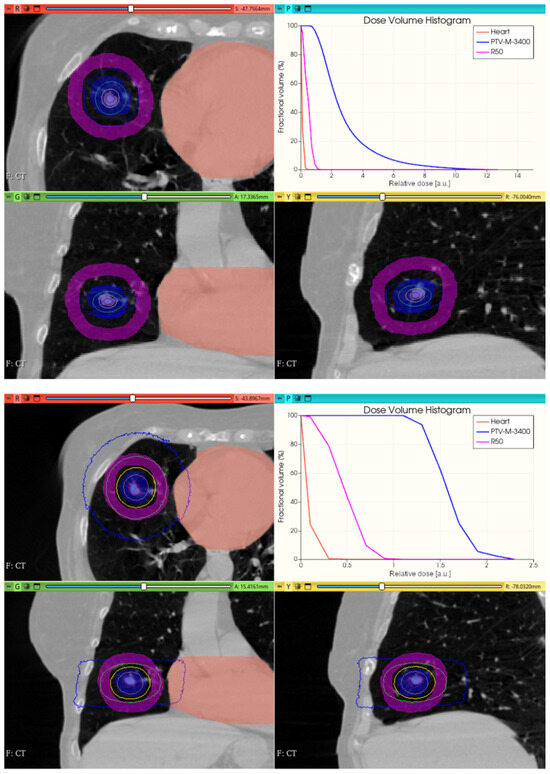

3.3.2. Preliminary CONVERAY Dosimetry Performance for Thoracic Irradiations